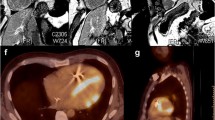

In a recent Danish study of 197 screened patients with systemic sarcoidosis, of patients with positive Japanese Ministry of Health and Welfare (JMHW) criteria, 53% were diagnosed by CMR alone compared to 29% with EMB [41]. Part of current diagnostic guidelines for CS, as published by the Heart Rhythm Society, includes late gadolinium enhancement (LGE) on CMR which is present in 97% of patients diagnosed. Similar to 2D-echocardiography, CMR allows for increased image clarity without added radiation risks, as well as the ability to differentiate between ischemic and non-ischemic lesions. Allergic reaction rates are also low, with only 0.005% of patients in a 37,788-patient cohort experiencing severe allergic reaction to gadolinium [42]. Additionally, in patients with a known glomerular filtration rate (GFR) greater than 30 ml/min, gadolinium contrast is considered to be low risk, and with recent advancements and development of newer contrast agents, reported complications (i.e., nephrogenic systemic fibrosis) are even lower [43]. Compared to echocardiography, CMR offers superior visualization of granulomatous infiltration, fibrosis, perfusion defects, and even microvasculitis [44]. As previously mentioned, the presence of LGE on CMR is a diagnostic criterion for CS in several established society guidelines. Late gadolinium enhancement is caused by delayed clearance of gadolinium in fibrotic myocardium [45]. The presence of myocardial scarring detected by LGE on CMR in a non-vascular distribution or in two orthogonal views without the presence of another known LGE process, like myocarditis or hypertrophic obstructive cardiomyopathy, is indicative of CS. The most prevalent myocardial fibrosis patterns detected as LGE on CMR in patients with diagnosed CS include sub-epicardial and mid-wall enhancements of the basal septum or inferolateral wall [46]. This modality of imaging also offers great detail of the right ventricle, often difficult to visualize using conventional 2D-echocardiography. It has been previously documented that right ventricular structural and functional changes may correlate directly with myocardial infiltration or be a result of pulmonary sarcoid involvement [47]. Isolated right ventricular involvement is rare, with large majority of patients rather having concomitant extensive left ventricular involvement. Right-sided involvement may often be patchy/multifocal [48], septal, or present with insertion point enhancement [49•]. Ventricular insertion point enhancement has been documented [50•] and directly correlates with pulmonary arterial pressures, right ventricular mass, volume, and ejection fraction. In cases of predominant right ventricular involvement, CS can be differentiated from arrhythmogenic right ventricular cardiomyopathy by several features: an older age of onset, a non-familiar pattern, wider QRS complexes, septal involvement with atrioventricular conduction disease, multiple arrhythmogenic foci, concomitant left ventricular disease, and the presence of mediastinal lymphadenopathy, all favoring sarcoid [51].

In diagnosis of CS, T2-weighted CMR sequences have been able to identify areas of definitive myocardial fibrosis for endomyocardial biopsy, increasing the successful detection of pathologic tissue [52]. Although LGE is not a diagnostic criterion by the modified JMHW guidelines, it has been shown that LGE is up to twice as sensitive than JHMW criteria [40, 49]. Additionally, presence of LGE on CMR was directly correlated with significantly higher rates of sudden cardiac death, ventricular arrhythmias, and all-cause mortality (11.9 vs 1.1%) in a meta-analysis of 10 studies (760 patients) [53]. Myocardial scarring identified on CMR via LGE has also been proven to be a potent independent risk factor for death, ventricular arrhythmias, and defibrillator discharges [54•]. Right ventricular involvement was also found to be predictive of ventricular tachyarrhythmias, probably because of higher coexisting left ventricular disease and resulting systolic dysfunction [48, 55, 56]. Newer techniques including circumferential strain (Ecc) and strain change per second (Ecc rate) to better detect focal myocardial damage have shown promising results in small patient samples, particularly in LGE-positive segments [57]. Given these mentioned findings, cardiac magnetic resonance imaging will remain a valuable tool in the evaluation process for suspected CS.

Despite several disadvantages and radiation risks associated with 18F-FDG PET, several studies have shown increased sensitivity and specificity when compared to other imaging modalities, including Gallium-67 uptake studies, Thallium-201 perfusion studies, and 99mTc imaging [60,61,62]. Some of its main advantages when compared with CMR are the ability to perform the tests in patients with implantable cardioverter-defibrillators and the ability to distinguish active inflammation from scar [63]. A recent small study out of France on patients with biopsy-proven sarcoidosis and suspected cardiac involvement reported 100% sensitivity and 91% specificity of FDG-PET/CT findings according to JMHW criteria [64].

There are limited studies comparing CMR to 18F-FDG PET, but one small study suggested that 18F-FDG PET has higher sensitivity (88%) when compared to CMR (75%). This study was quite small however, with only eight patients, and the results were not statistically significant [58, 65•]. A list of studies utilizing CMR and PET in patients with systemic sarcoidosis, known or suspected CS, and their respective sensitivities/specificities for cardiac involvement identification can be seen in Table 1. Initial reports also assume benefit of PET to reliably monitor disease progression and therapeutic monitoring of anti-inflammatory or immunosuppressive therapy [90] for CS, response to ablation therapy in ventricular arrhythmia patients using lesion metabolic activity (LMA) which correlated with a 20-fold higher risk of MACE in non-responders (p = 0.007) and may even parallel systolic function (p = 0.003) [91•], and association with higher adverse event rates in those with high-degree AVB [92]. Novel ECG parameters of ventricular remodeling (septal and inferolateral) and diffuse QRS fragmentation have also been found to have a strong association with myocardial FDG uptake on PET scans in sarcoidosis patients in a recent Finnish study of 133 patients [93]. FDG PET has also been shown to diagnose CS in asymptomatic patients [94] as this modality allows for detection of inflammation and infiltration via metabolic activity at the cellular level [95•]. In addition, in cases where myocardial LGE usually persists and T2-weighted edema CMR imaging may be unreliable, PET can reveal reduced FDG uptake that can signify a successful response to therapy in myocardial CS [96, 97].

Imaging classification for CS includes normal results (normal perfusion and 18F-FDG uptake), progressive disease (a moderate perfusion defect and increased 18F-FDG uptake), and fibrous disease (severe perfusion defect and minimal or no 18F-FDG uptake) [66]. Additionally, other quantitative techniques with 18F-FDG PET have been developed, like FDG-volume intensity detection, coined cardiac metabolic activity (CMA), which has been independently associated with adverse cardiac events in patients with CS [98•]. In summary, both imaging modalities, 18F-FDG PET and CMR, are very useful in CS and can be used in conjunction to diagnose and evaluate CS. Fibrosis can be identified as LGE on CMR, and inflammatory infiltration can be detected via increased 18F-FDG uptake on PET. Each modality can highlight different pathophysiologic processes in CS, and for this reason, both studies are valuable tools to diagnose and monitor the progression of the disease process.

F. Simultaneous hybrid cardiac imaging: 18F-FDG PET/CMR

Recently, some centers have taken on a hybrid imaging approach by combining 18F-FDG PET with CMR [115]. A small single-center study (N = 51) compared simultaneous 18F-FDG PET and LGE on CMR to current accepted diagnostic imaging modalities (18F-FDG PET alone and CMR alone). This study found that simultaneous hybrid imaging was superior to conventional imaging in terms of sensitivity (94%), specificity (44%), positive predictive value (76%), and negative predictive value (80%). The sensitivity for 18F-FDG PET is 85% and LGE on CMR is 82%. The prevalence of CS in this patient population was 65% (N = 33) [88]. Simultaneous hybrid cardiac imaging allows for high-resolution morphologic and functional data collection via LGE-CMR [95•] while retaining the ability to assess for myocardial viability, perfusion, inflammatory metabolism processes, and abnormal cardiac deposition via 18F-FDG PET. Compared to PET-CT, 18F-FDG PET CMR offers many advantages, including attenuation correction without additional radiation, detection of edematous tissue, and improved image quality in regard to myocardial viability, perfusion, cardiac morphology, and function [95•]. Recent studies also predict that hybrid cardiac imaging may allow clinicians to differentiate between active and inactive disease, as both positive PET and LGE on MRI suggest active CS, while PET-negative and LGE MRI-positive imaging may correlate with inactive disease with residual fibrosis [95•]. This mentioned benefit may aid in the monitoring of CS and response to therapy [116]. As both 18F-FDG PET and CMR are indicated imaging studies for the evaluation of CS [83], and there is no clear consensus on which modality is superior [104, 117], simultaneous hybrid cardiac imaging should be considered.

Framework of combined PET/CMR studies establishes a new monumental mark in our role as imagers and caregivers for these patients. The combination of CMR and FDG-PET imaging may add significant incremental benefit for many patients. Vita et al. demonstrated this in a recent paper with utilization of CMR, FDG-PET, and combination of both in assessment of the likelihood of CS and guidance of patient management. The combination of FDG-PET and CMR image data reclassified 45% (high probable and higher likelihood groups) of patients compared with single-modality imaging [118•, 119]. On the contrary, Dweck et al. postulated in a recent prospective combined PET/MRI study only 32% of their patients with both PET and MRI (LGE)-positive tests to suffer from active CS. As mentioned previously, it is important to keep in mind that PET-negative findings with positive LGE in MRI can be rather considered as inactive CS with remaining scar [87, 95•].